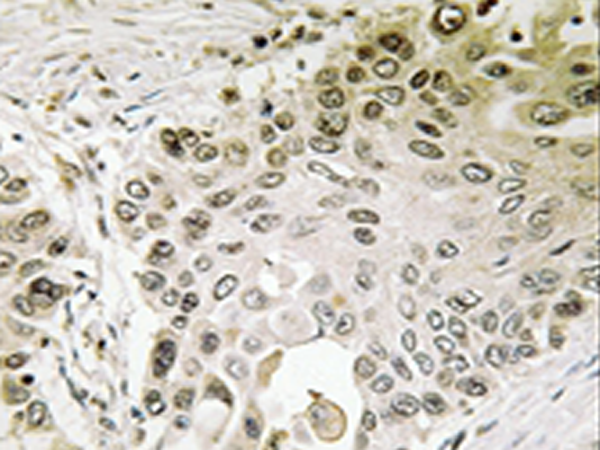

IHC |

IHC positive control: |

Human lung carcinoma tissue |

IHC Recommend dilution: |

50-100 |